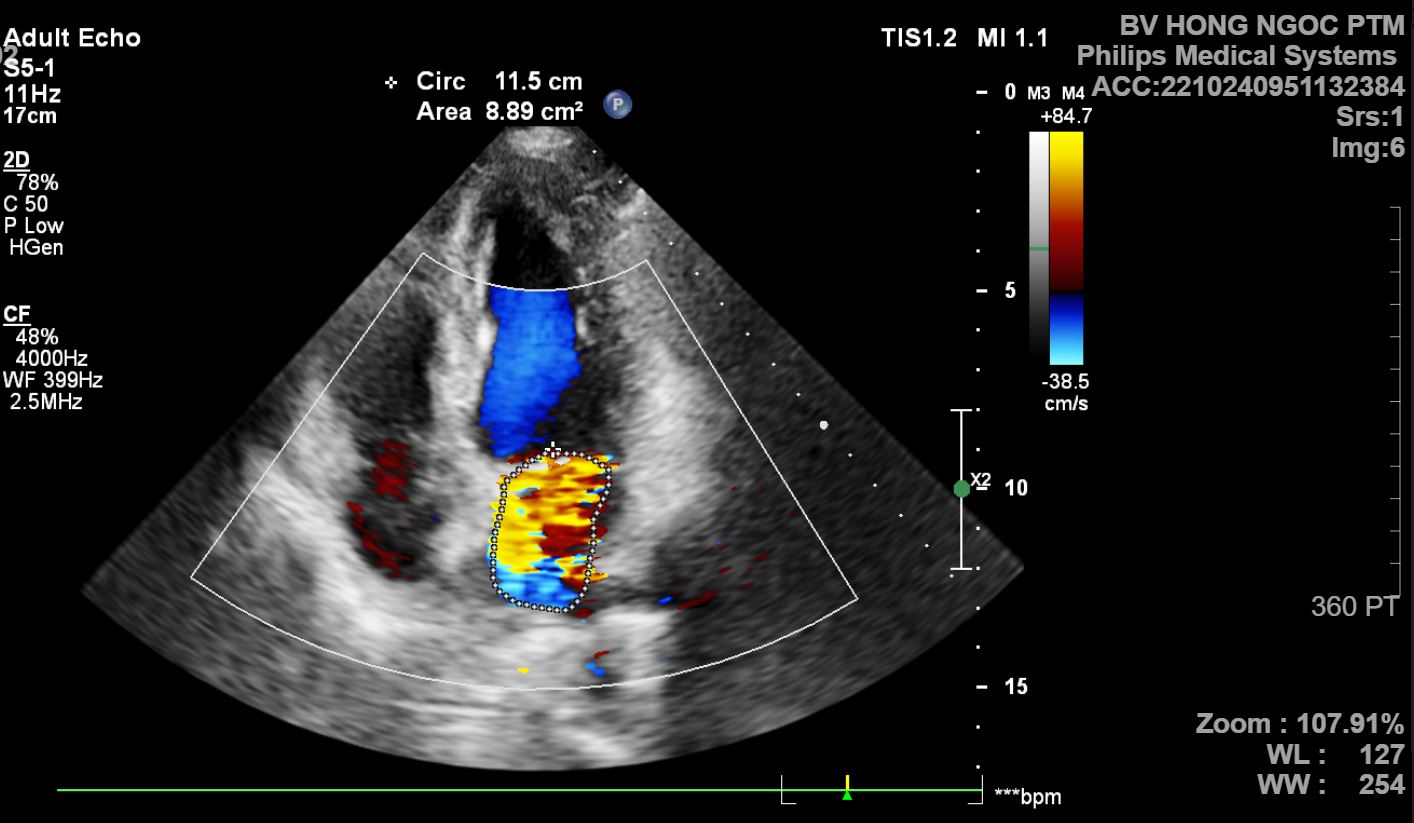

Như trường hợp anh T.Đ.C, 60 tuổi ở Hưng Yên. Bệnh nhân có tiền sử khỏe mạnh, không có bất cứ triệu chứng cơ năng trên lâm sàng nào, chỉ đến bệnh viện để khám sức khỏe tổng quát. Kết quả siêu âm tim cho thấy bệnh nhân có van hai lá hở nhiều.

hình ảnh siêu âm bệnh lý cấu trúc tim Hình ảnh siêu âm tim của bệnh nhân N.Đ.C